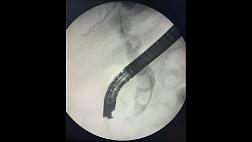

Рис.2.5. Схема выполнения эндоскопической перфузионной папиллосфинктероманометрии.

Рис.2.6. Графическое изображение параметров эндоскопической папиллосфинктероманометрии.